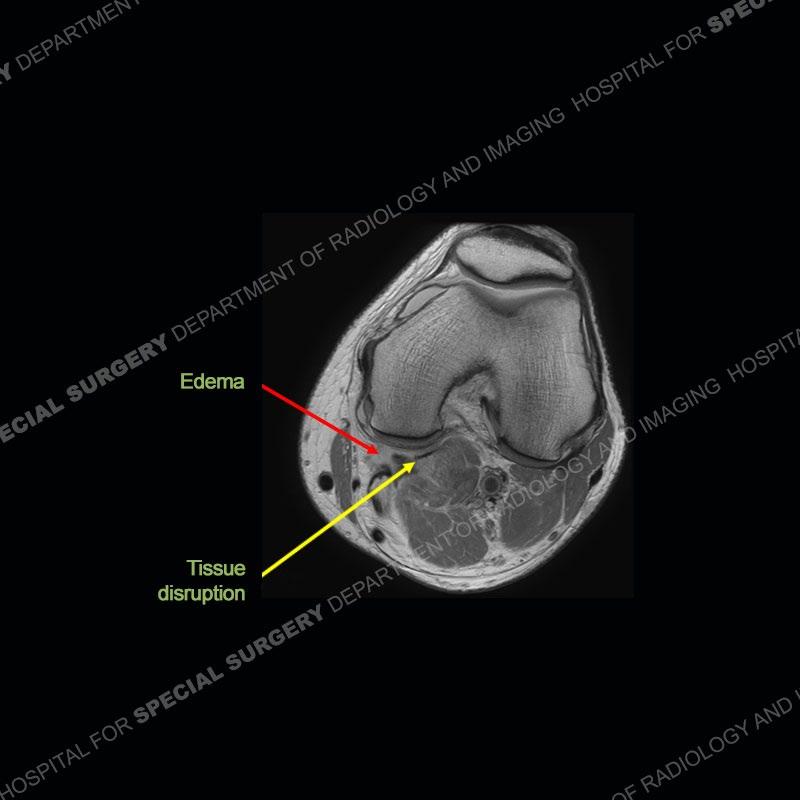

Findings

The radiographs show degenerative change of the medial compartment and a varus knee, but they are not germane to this case. No acute bony injury is present. The MRI shows edema of the posterior medial knee/soft tissue and a focal area of a partially disrupted low signal structure. The details are kept at a minimum in the findings of this case on purpose.

Diagnosis: Partial Disruption Medial Head Gastrocnemius (MHG)

The findings were kept purposefully vague as identifying the structures early on takes away a lot of the diagnosis. An uncommon entity and one of which we do not see a lot. Enthesopathic changes and tendinosis are seen as are distal MHG injuries, but proximal tears are rarely present. This case highlights a number of points. One, it almost always comes down to anatomy. Perhaps not a structure we normally spend too much time on, except save for diagnosing a Baker’s cyst, but knowing where this structure and all structures exist in all three planes is imperative. Second, when you think you are making a “call” or finding that you have never made before, step back and think is this just the abnormal presentation of a common pathology. That situation arises much more frequently. Third, if you look at it once, twice, and probably a third time and are confident in your odd or very rare diagnosis, stick to your guns. Especially, when it comes down to anatomic structures, the proof will be in the images.

Fourth, use all imaging planes and different pulse sequences to make your diagnosis. The edema highlighted in this case can be seen as the obscuration of fat on the PD images but is much easier to perceive as the high signal on the IR pulse sequences. The actual disruption of the MHG myotendinous junction is only able to be seen on the axial images. On the sagittal and coronal images, we get a sense something is wrong but hard to be exact. Lastly, when you look at a study and something just seems off (as I would say the sagittal and coronal images do with that dark band of tissue posteriorly), listen to yourself and go through the study slowly and meticulously. Most of the time you will find you were right, and something indeed is present.